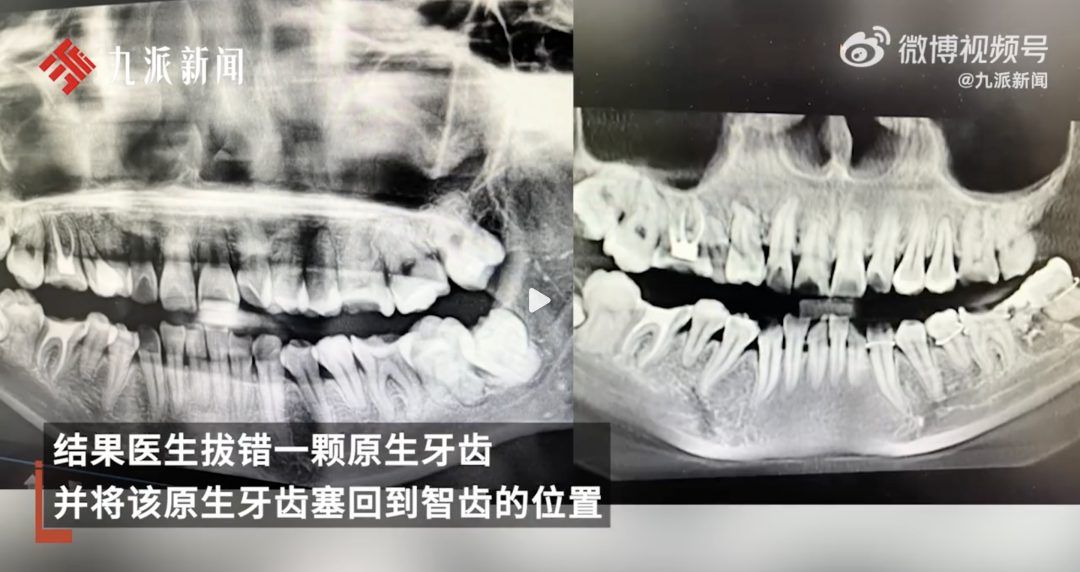

近日,一女子在医院拔智齿被拔错牙齿,事后医生隐瞒修改了病历,后续维权未果,从该医院11楼坠楼身亡。对此,安庆市卫健委一值班人员称,已知晓此事件,相关部门已经在调查处理,有专人负责处理。